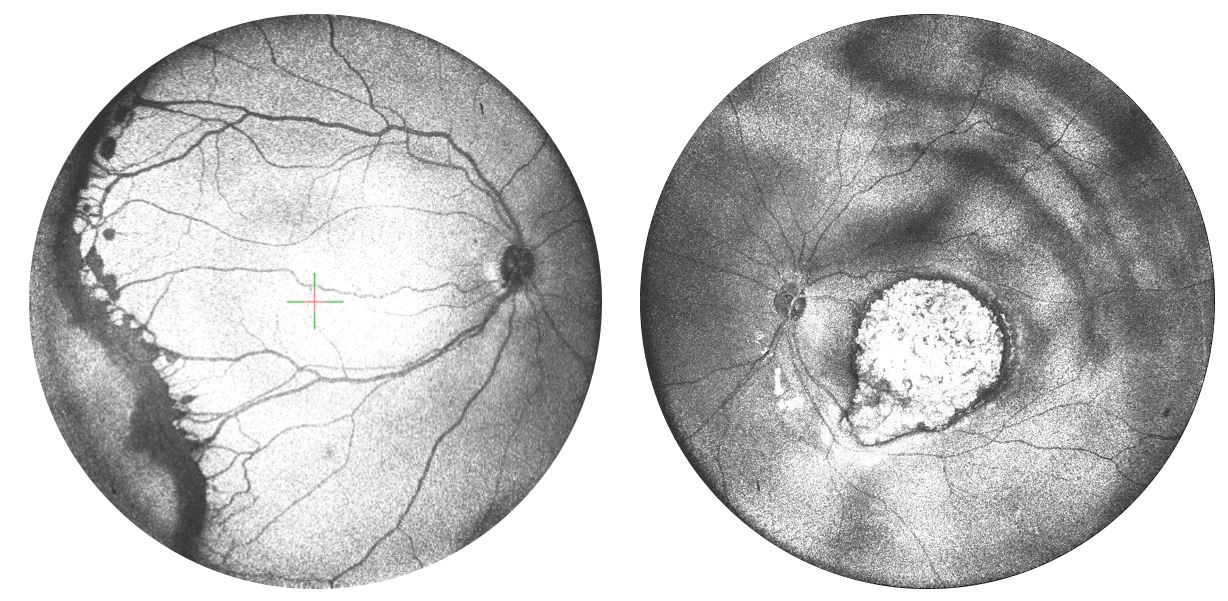

Retinal images taken using a new OCTA device of ROP and retinoblastoma

(Left) En face OCT image with a clear demarcation line from an infant (ROP, Stage 3) with preretinal neovascularization acquired by the handheld 105-degree OCT. (Right) En face OCT showing an elevated tumor from a 5-month-old patient with bilateral retinoblastoma.